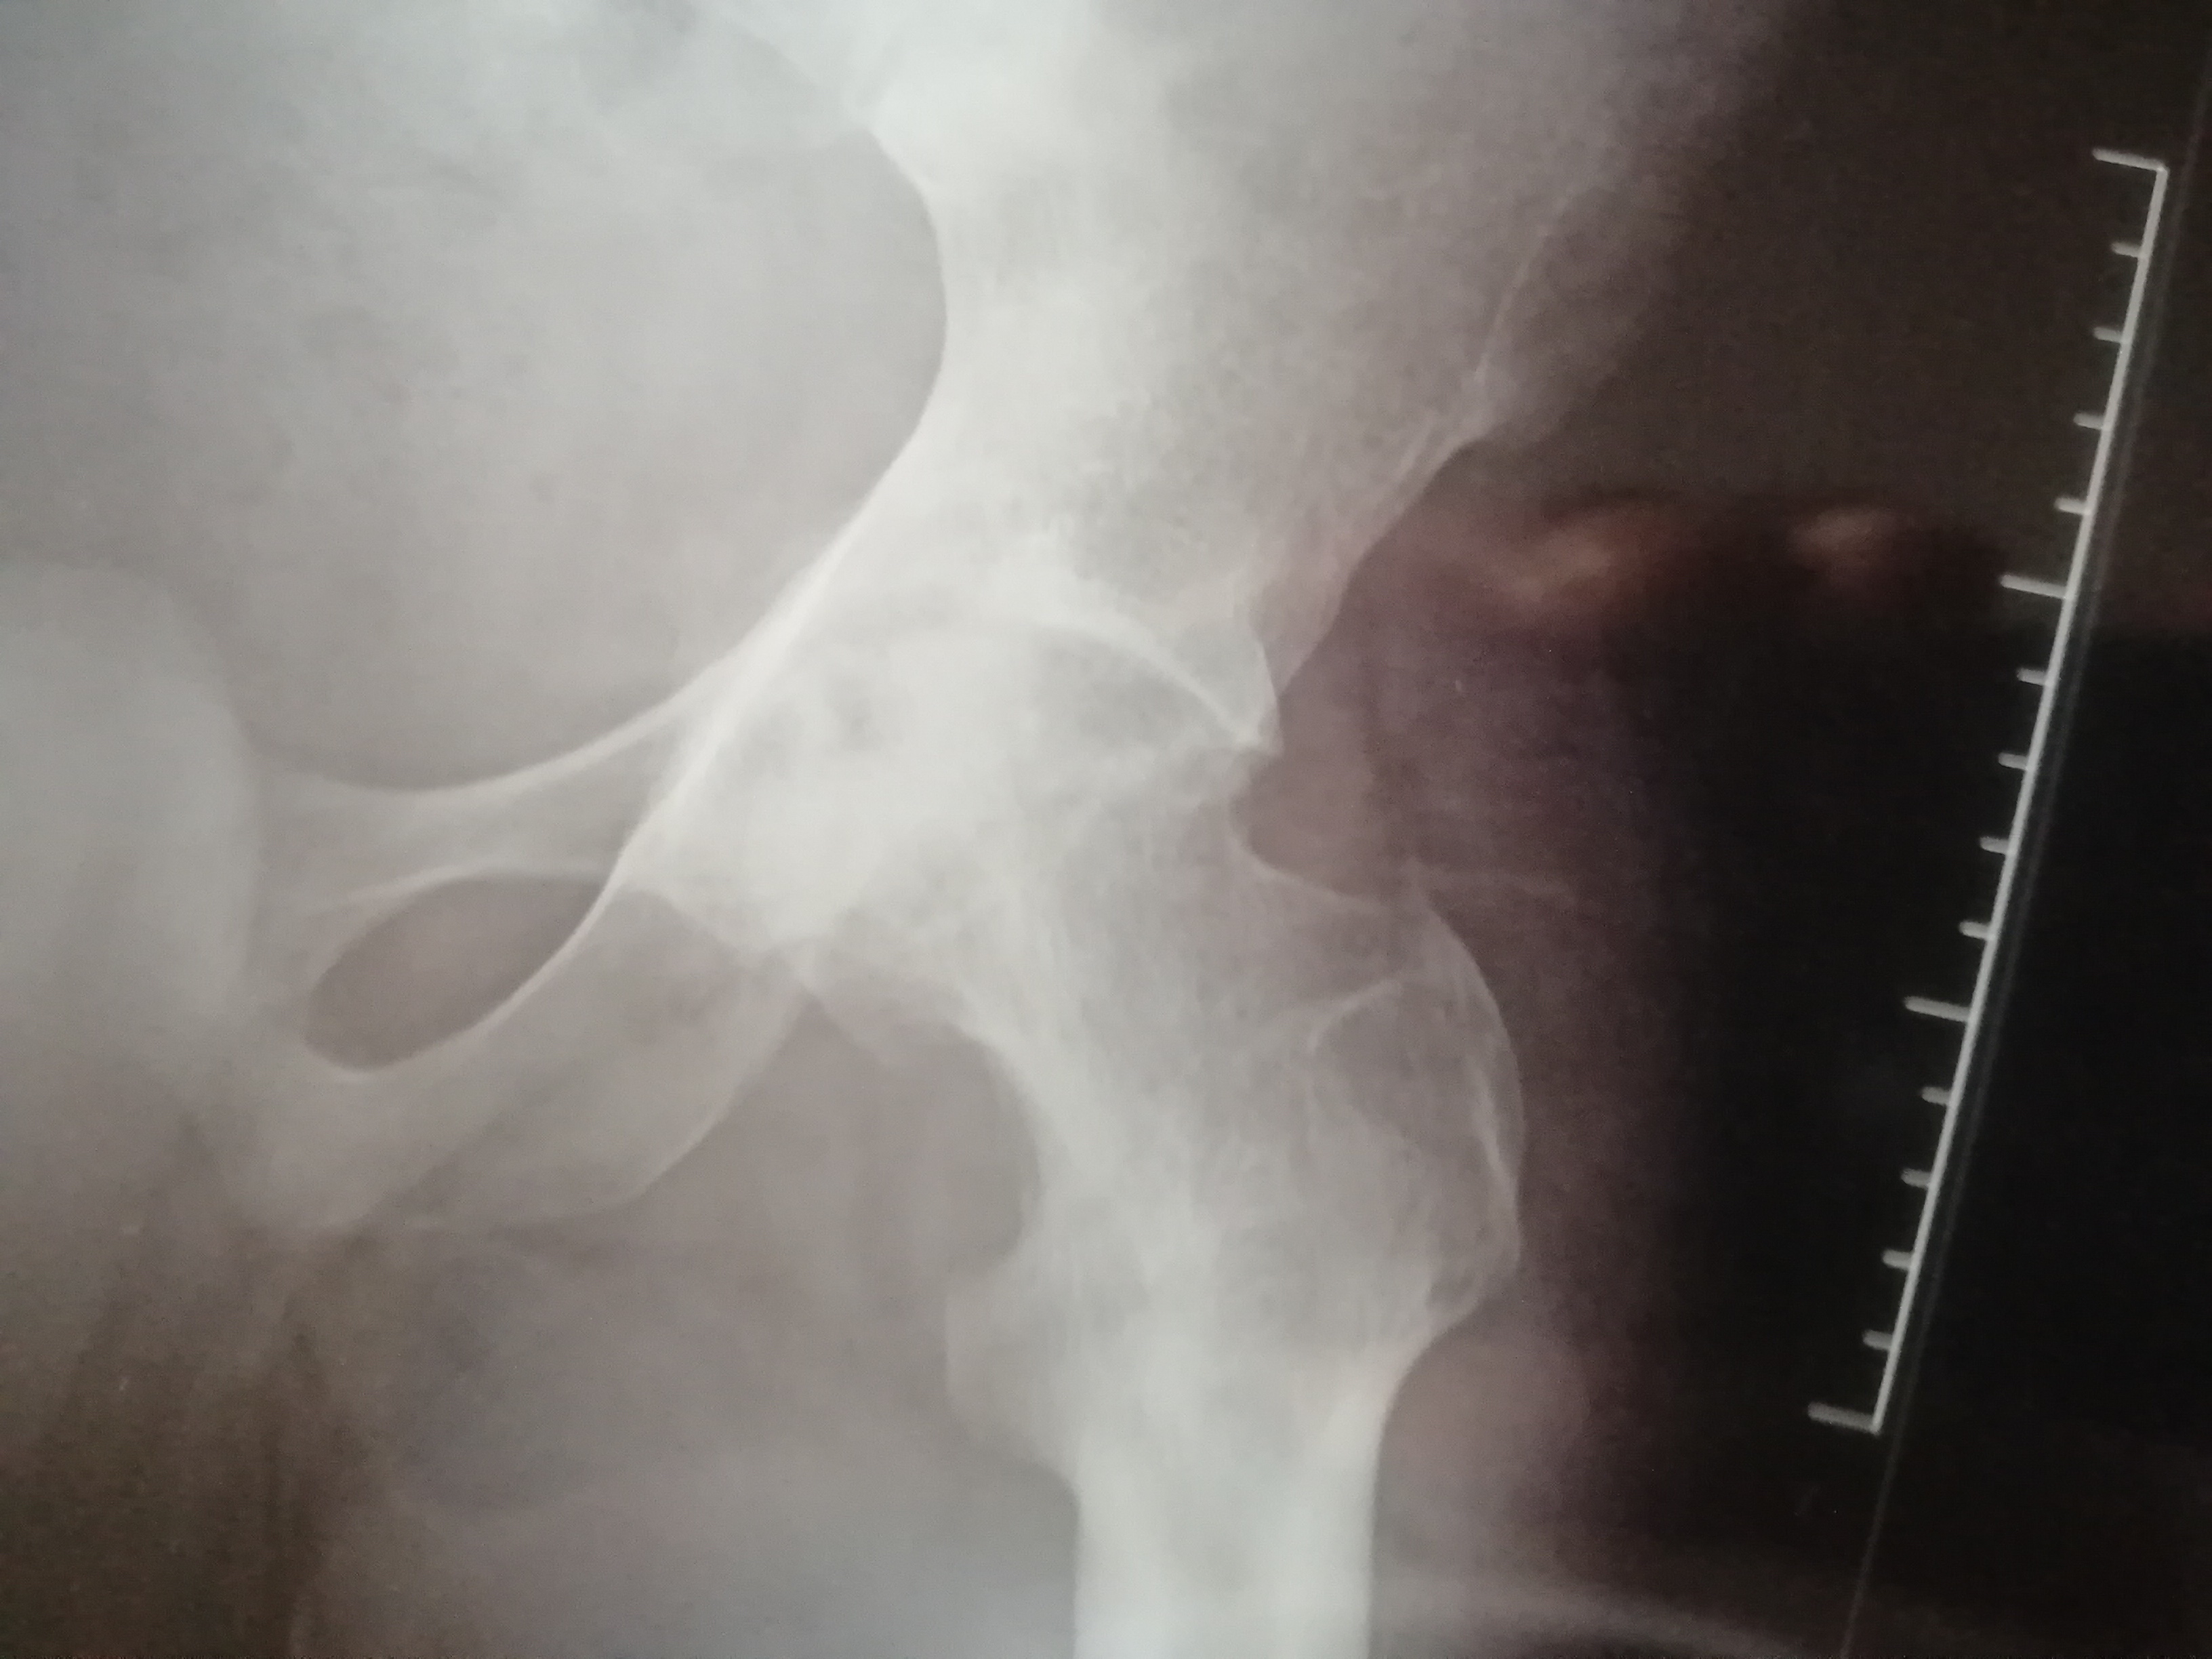

Through her resilience, i went to college and acquired a qualification as a Class 1 Mechanical Fitter and Turner. Because of the nature of the disease, i developed Avascular Necrosis of the hip which has worsened to the point of immobilising me. A second complication has also happened which is call Fixed Flexction Deformity (FFD) which has caused my leg to bend and lock in a permanent position making it extremely difficult to walk let alone work to earn money for the surgery which my medical insurance does not cover and also which i could never afford even if i was working full time.

The funds will be used exclusively for the Hip replacement surgery. Getting back on my feet is my number one priority. Getting back to working for my self, family and community very important to me and my wellbeing as a you adult. I would personally give up anything to be able to walk again. I will include necessary documents to help you understand me and my situation. I will include old and recent radiographs showing the progression of the damage the condition had done to the left hip.